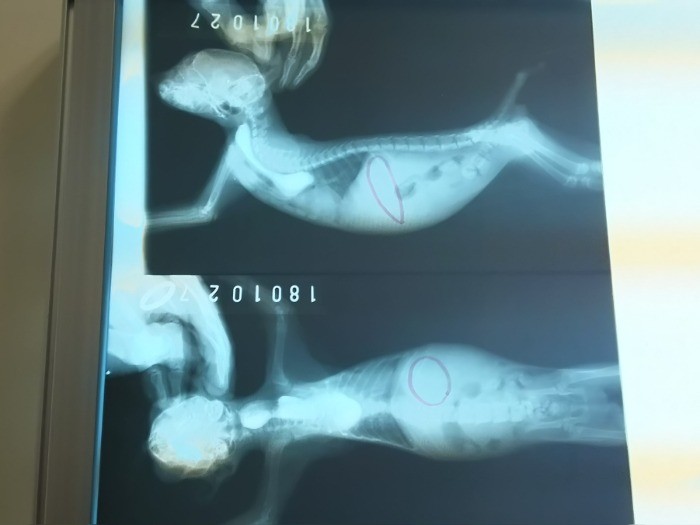

Share 緊急手術! 保護した子猫に「胃ろう」 ギャラリー 2019/02/17 1 / 10 sippoのおすすめ企画 連載「保護猫の迎え方」 猫を家族に迎えたいと思ったら、選択肢に保護猫も入れてみませんか?連載「保護猫の迎え方」では、7回にわたって保護猫の迎え方を詳しく紹介していきます。 関連タグ 保護猫子猫動物愛護団体動物愛護センター動物病院病気介護栄養 タグ一覧 Follow Us! 犬や猫との暮らしに役立つ情報をお届けします。 Facebookをフォロー Xをフォロー Instagramをフォロー